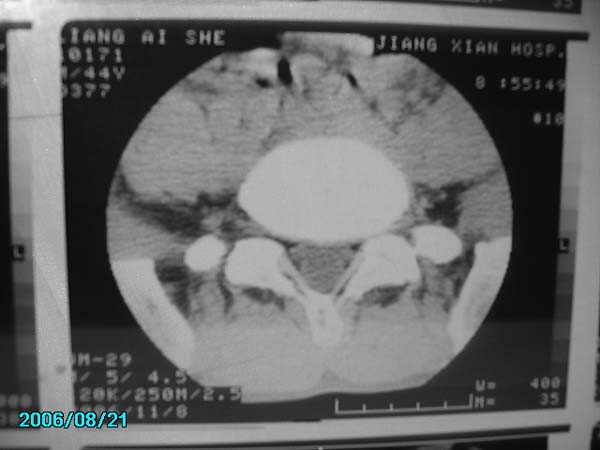

男,40岁,腰疼半年

腰4-5椎间盘后缘变平直,可考虑椎间盘轻度突出。余未见异常。

l4/5椎间盘膨出。

腰4-5椎间盘轻度突出。余未见异常。

腰椎侧弯,l4-5椎间盘膨出。

腰4-5、腰5-骶1椎间盘后缘变平直,可考虑椎间盘轻度突出。余未见异常

腰4-5椎间盘轻度突出。余未见异常

除有第3-5腰椎椎体后缘中央血管沟显示外,诸椎间盘比较正常。我也象13081830109战友那样看见了指纹,呵呵。

部分层面有轻度彭出。